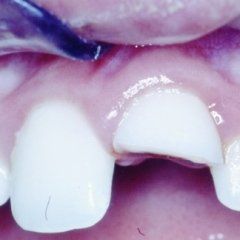

Odontoiatria e conservativa

L’enorme diffusione ancora oggi riscontrabile della carie dentaria, unita a traumi, difetti di mineralizzazione o ipoplasie dello smalto determinano la necessità di dover ricorrere ad un restauro dei tessuti dentari lesionati. Il continuo miglioramento dei materiali e di conseguenza delle tecniche hanno altresì ampliato il raggio di azione della cosiddetta conservativa che con il ricorso al trattamento endodontico in caso di lesioni particolarmente gravi, occupa circa i due terzi dell’attività del dentista. In considerazione di questo fatto quindi, oltre all’evidenza che il trattamento restaurativo diretto è in genere il primo atto odontoiatrico che si effettua su una corona dentale lesionata, emerge la necessità che questa terapia sia ben eseguita ed in armonico rapporto con le strutture parodontali ed endodontiche.